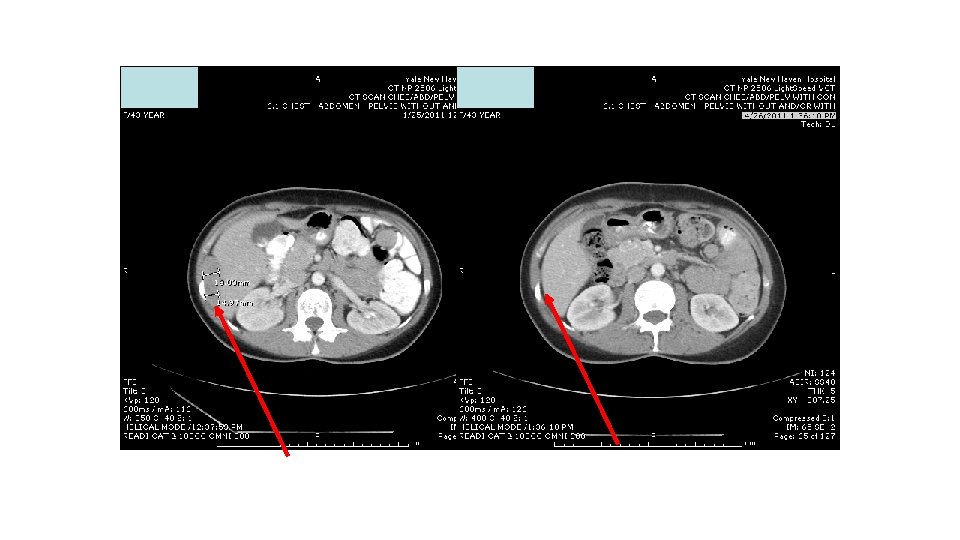

Response to ipi/anti-PD 1, 3/1 dose level